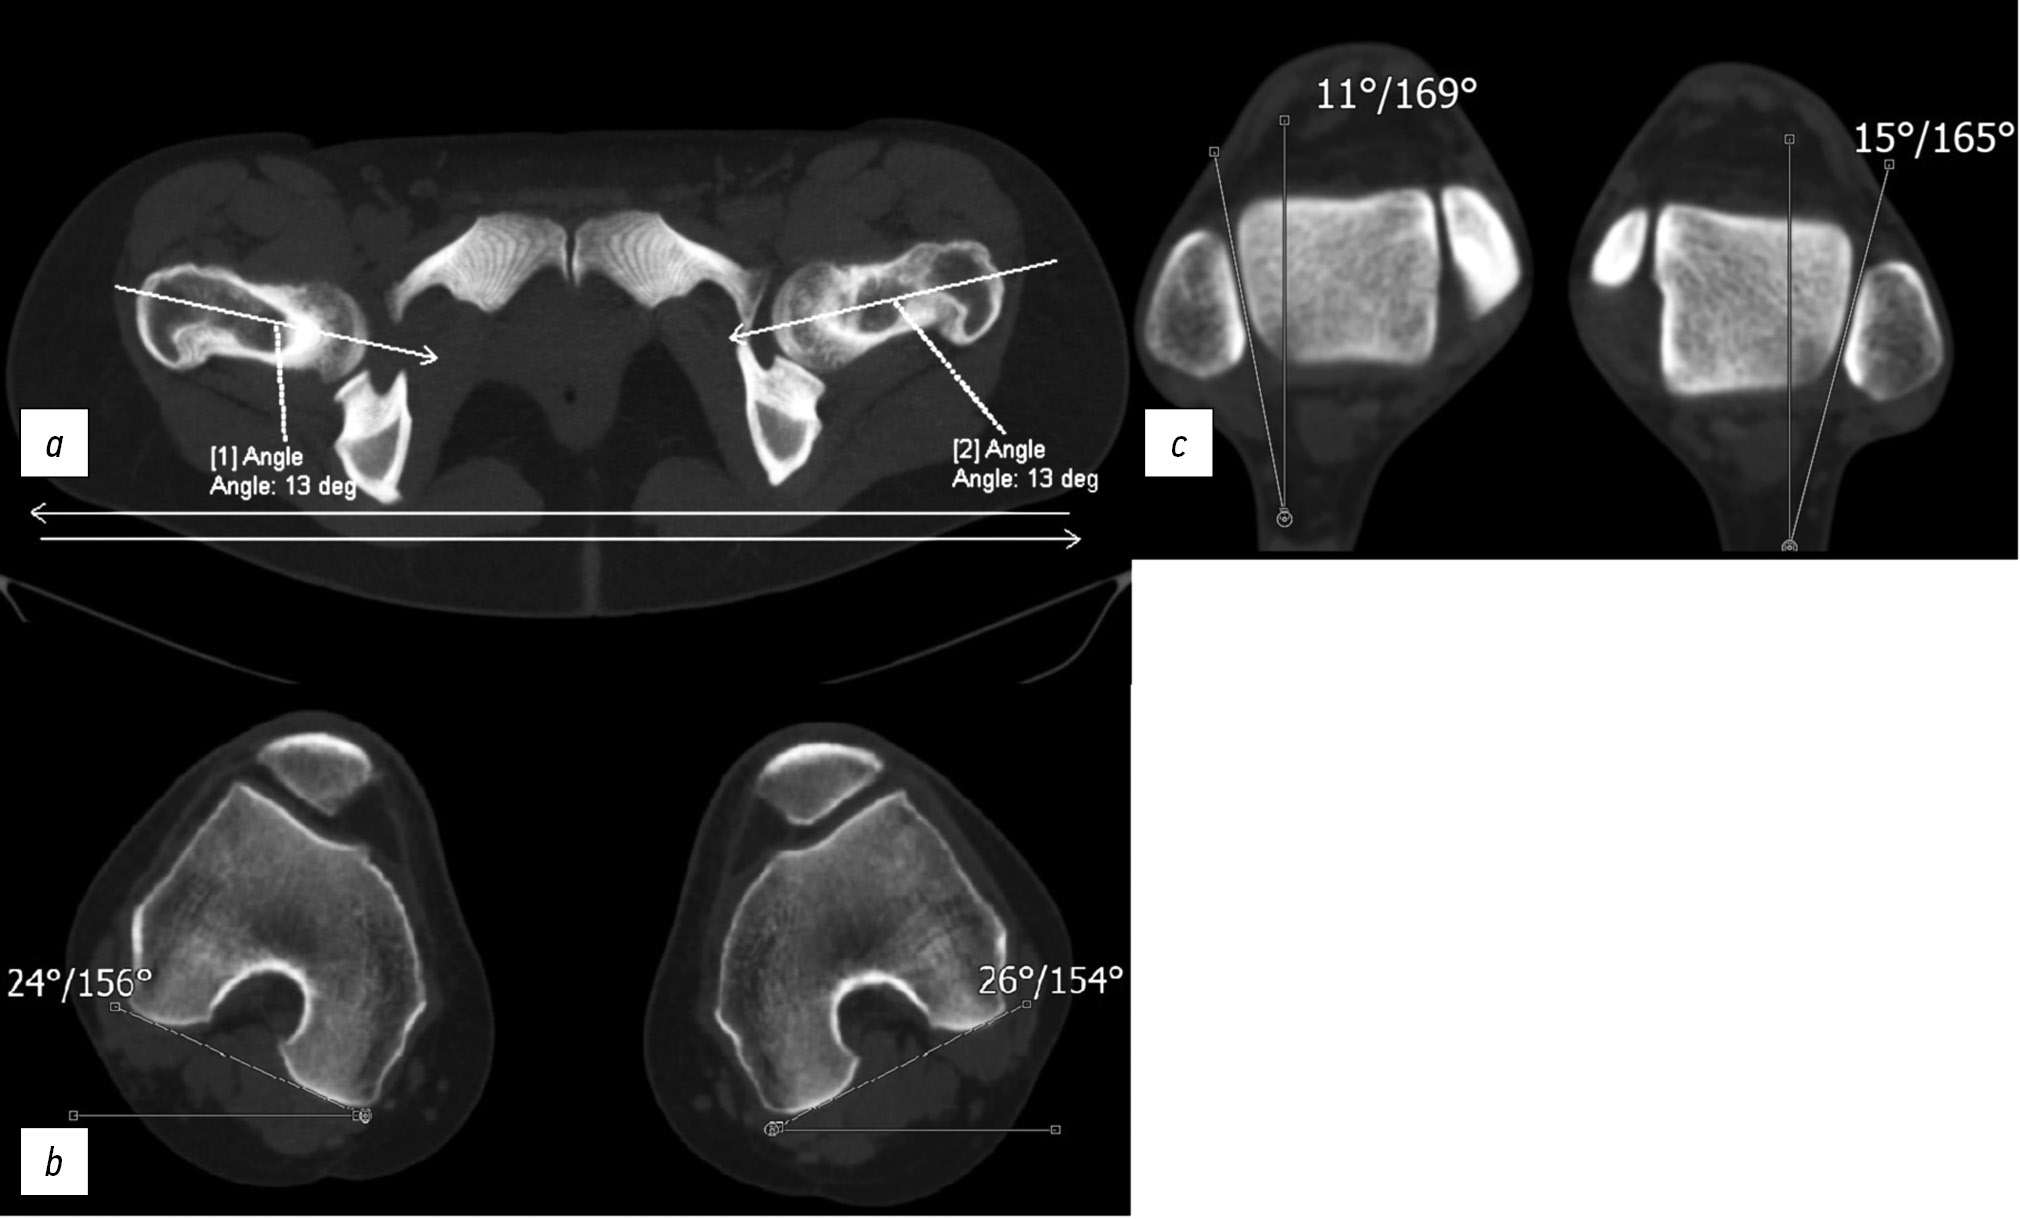

На аксиальных срезах тазобедренного, коленного и голеностопного суставов изучали торсионную характеристику бедренных, большеберцовой костей, а также интегрированную торсию нижней конечности от тазобедренного до голеностопного сустава. При этом определяли следующие углы:

- угол отклонения от фронтальной плоскости линии, расположенной по середине шейки бедра основанием, находящимся на вертельной области — α; если этот угол открыт кзади, то его обозначали знаком (–) (рис. 2, а) [8, 9];

- угол отклонения от фронтальной плоскости линии, соединяющей мыщелки бедра по задней поверхности основанием, расположенным на внутреннем мыщелке — β; если основание этого угла находилось на наружном мыщелке, то его обозначали знаком (–) (рис. 2, b) [8, 9];

- угол отклонения от сагиттальной плоскости линии, расположенной по суставной поверхности лодыжки малоберцовой кости — γ (рис. 2, c) [8, 9].

Рис. 2. Аксиальные срезы тазобедренных (а), коленных (b) и голеностопных (c) суставов.

Fig. 2. Axial sections of the hip (a), knee nyh (b) and ankle (c) joints.

Сумма первого и второго углa составляет антеторсию (антеверсию) шейки бедра (норма 10–25 °). Если полученное значение <10 °, это характеризует величину угла ретроторсии (ретроверсии). Сумма второго и третьего углa (норма 20–35 °) соответствует величине угла торсии голени. Кроме того, необходимо оценить и интегрированную торсию нижней конечности (норма 10–20 °). Эту единицу мы высчитывали как разницу углов γ и α. Интегрированная торсия позволяет оценивать положение тазобедренного сустава по отношению к голеностопному [8, 9].